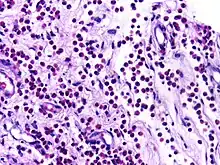

![]() | Plasma cells | Plasma cell showing eccentrically placed round nucleus with cart wheel like chromatin. | Category: Plasma cells | Plasma cell |